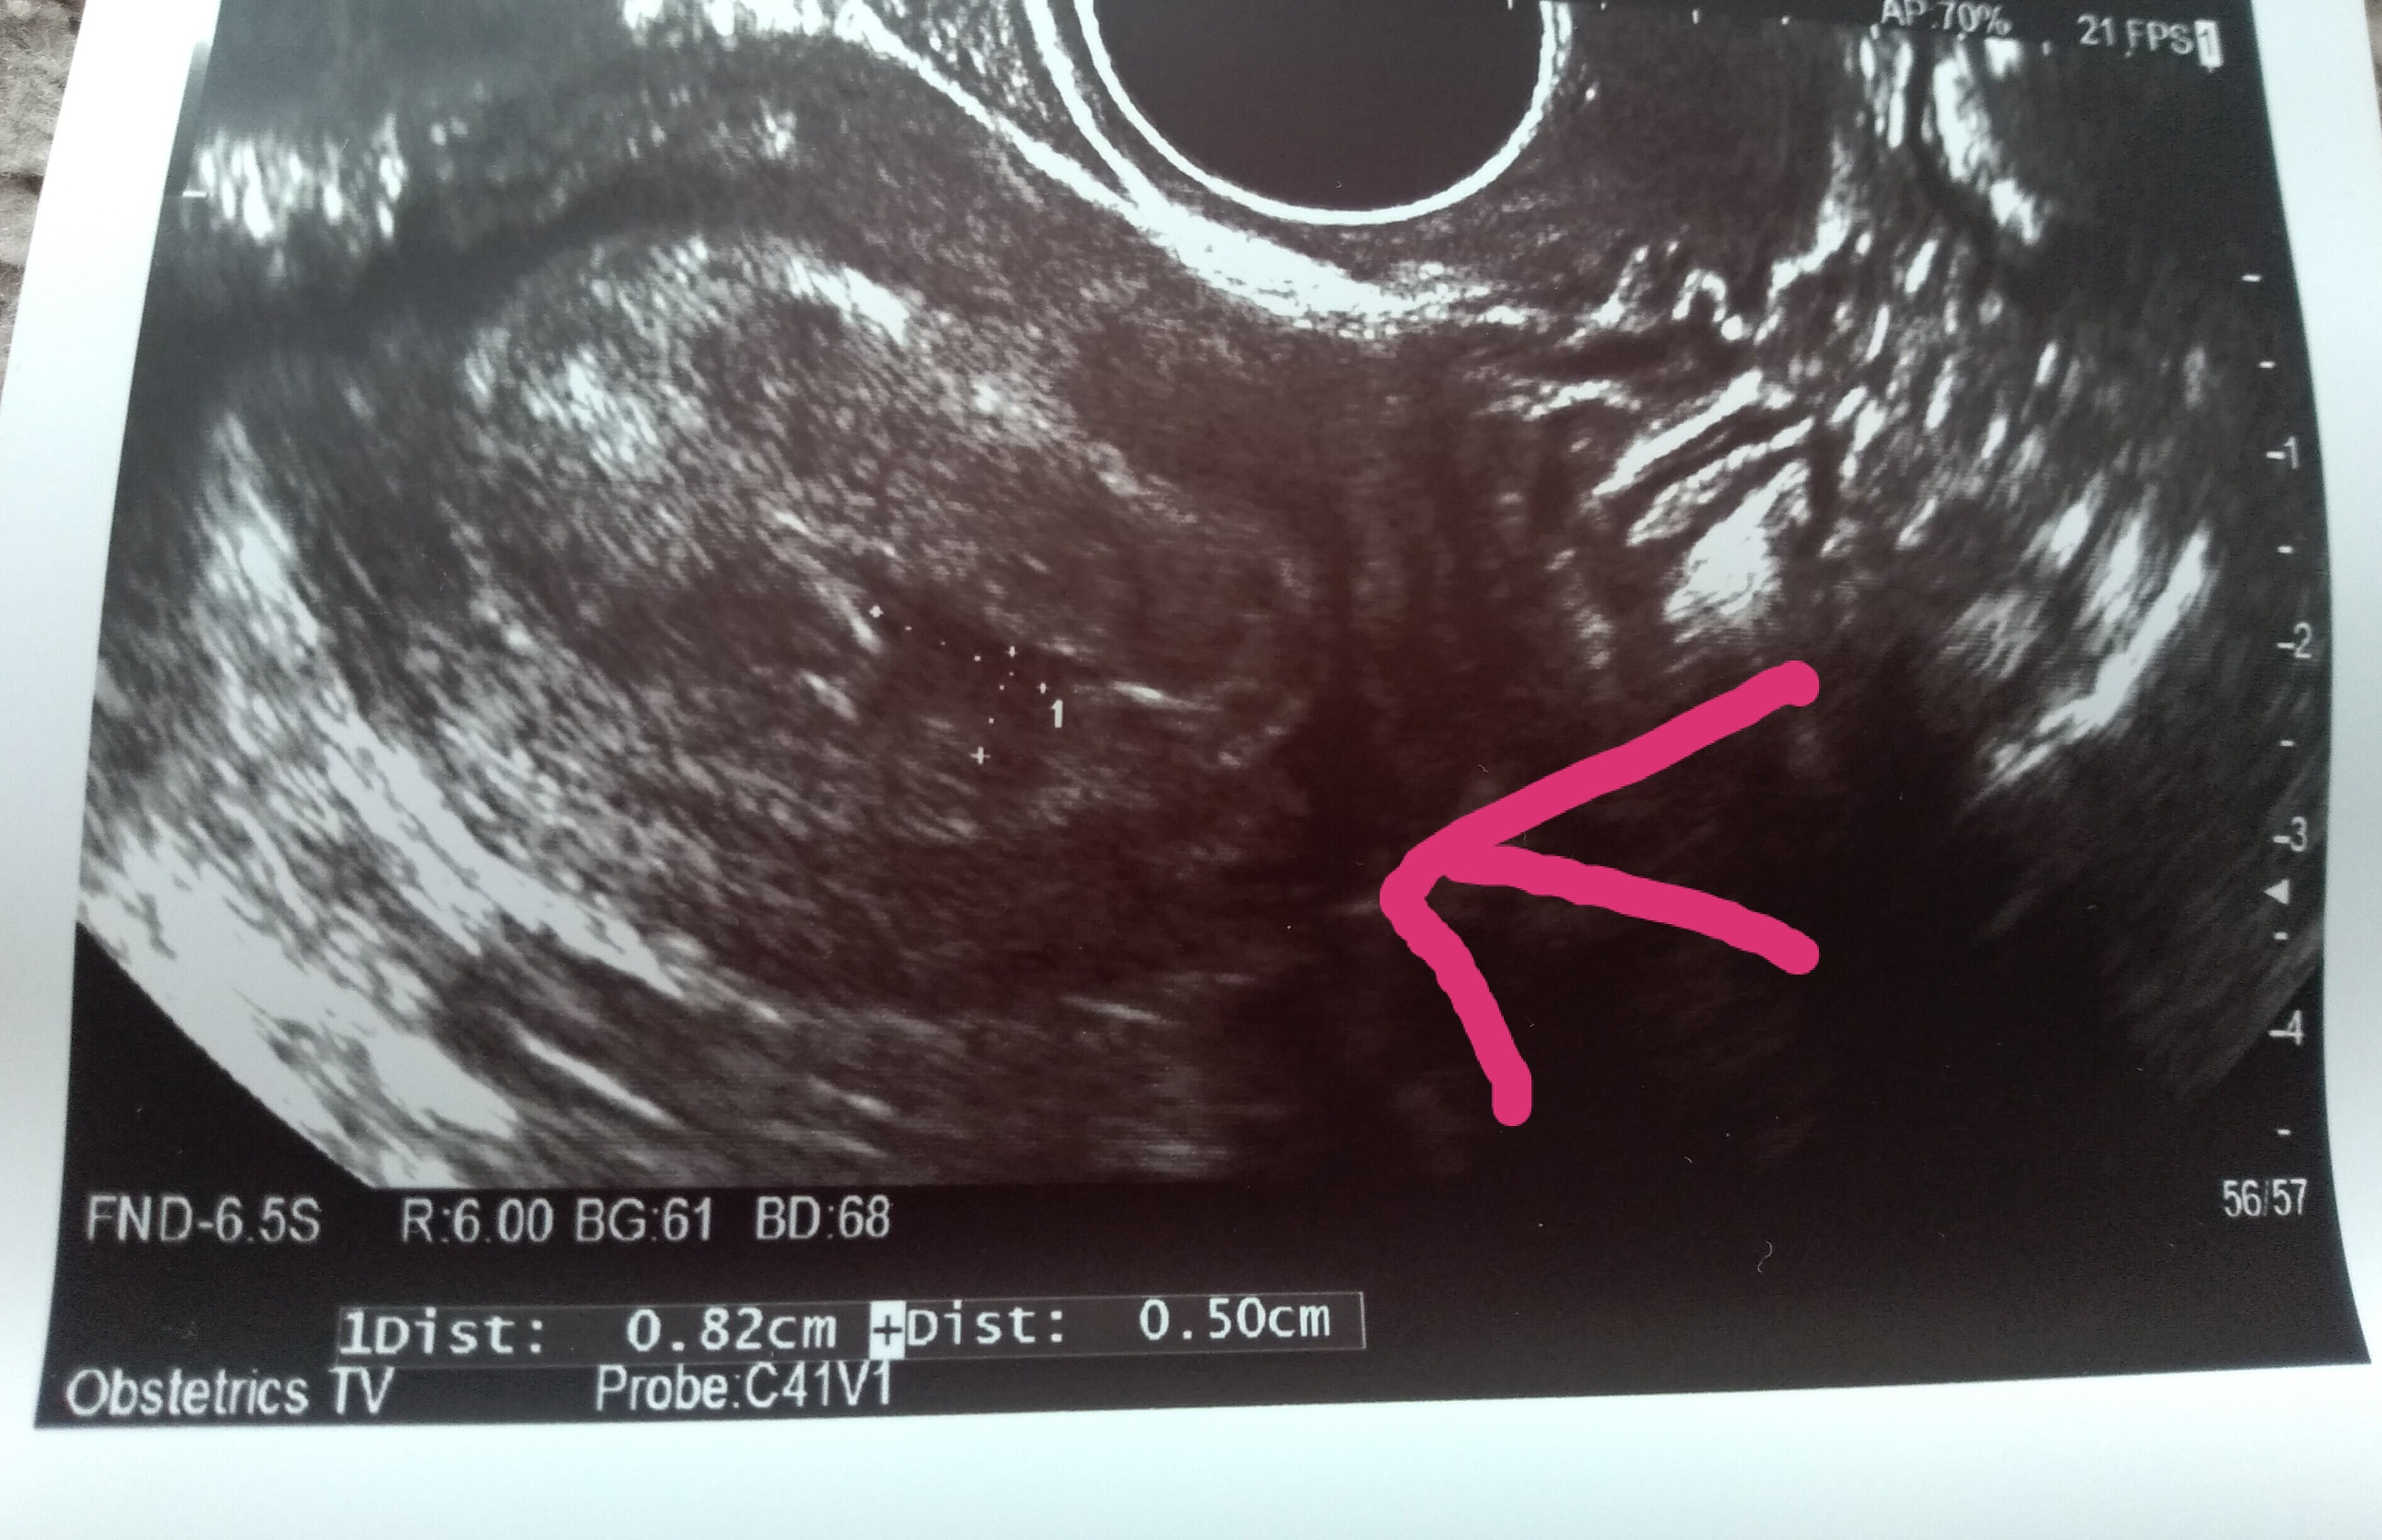

Rossig u mnie tez na ostatnim usg powinno byc juz widac wszystko a nie bylo, tylko pecherzyk i woreczek żółtkowy i tez mam krwiaka powiedziala mi ze moge krwawic, ze w najgorszym wypadku moze wciagnac zarodek tez nie wiem co bedzie, polska doktorka tj moja rodzinna dzwonila do mnie kazala lezec nic nie robic jedybie herbate i wstac do toalety, doskonale Cię rozumiem, moje usg następne 27.05 nie mogę się doczekać tak bardzo chcialabym wiedziec juz co z moim dzidziusiem, musimy czekac cierpliwie i miec nadziejeHej dziewczyny, byłam na usg. Nie wiem co o tym myślećpowiedziała, że pęcherzyk ciążowy jest za mały na swój wiek. Ma 1,21 cm. Według aplikacji dziś 6+1

jest zarodek 2,9 mm. Serduszko bije 111/min. Nie puściła mi do słuchania tylko liczyła, widziałam jak faluje.

Jednak ciąża jakby jest młodsza o 2 tyg - usg pokazuje 4+2

Nie mogłam później zajść o 2 tyg bo tydzień temu na usg usłyszałam, że ciąża jest o 3 dni starsza. Poza tym robiłam betę 28 dc i już była pozytywna więc nie mogłam mieć wtedy owulacji.

Dodatkowo mam krwiaka większego dwa razy od pęcherzyka ciążowego - ma 8 na 5 i obok jakieś jeszcze mniejsze...

W razie krwawienia mam jechać na izbę przyjęć... Powiedziała, że ciąża wysokiego ryzyka, mam tylko leżeć. Karty ciąży nie założyła. Kontrola za 2 tyg. Dołożyła luteine i teraz mam 3 x1 duphaston, 2x1 luteina

Miałam wrażenie, że mnie nastawia, że nic z tego nie będzie

Martwię się strasznie, to będą najdłuższe 2 tygodnie

Różowa strzałka wskazująca to krwiak. Te duże coś na 5 cm to nawet już nie wiem z tego wszystkiego co to było